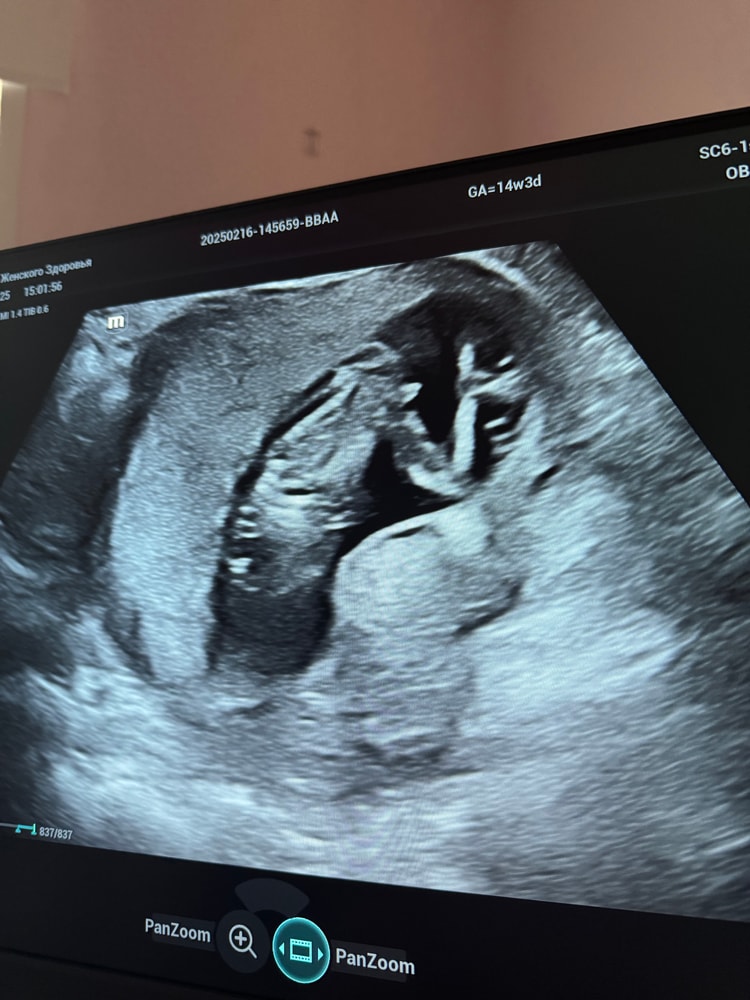

На втором фото 100% мальчик. Ну нет у девочки такого. Вот девочка, снизу, ничего н где не висит Изображение

Алина, и ниже у вас на фото это не нога, а яйца. А выше палочка сами знаете что

Алина, на фото можно подумать что яйца да)) Но это две ножки Просто видео сюда не подгружается я не знаю почему На видео эти два кругляшка двигаются ко всю и потом выпрямляются

Антонина, это мальчик, поверьте, я столько этих яиц перевидела. Из этой пи.пи.ськи пирожка не получится. У девочек не торчит ничего, а кофейное зернышко только между ног, сбоку вы у девочки не увидите ничего. А у вашего торчит